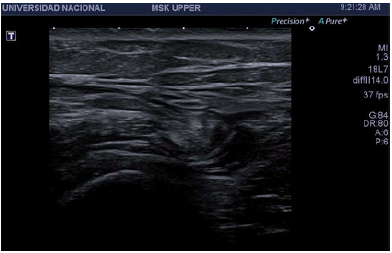

The patient underwent multiple analgesic (until being prescribed with hydrocodone + acetaminophen, which she takes irregularly) and anti-inflammatory treatments, and received multiple physiotherapy sessions without improvement; in fact, her symptoms increased progressively. After assessment by Orthopedics, she was diagnosed with bilateral snapping hip syndrome, with retraction of the tensor fasciae latae. An ultrasound of the hip was performed on both sides, finding thickening of the right tensor fasciae latae (4mm), alteration of the fibrillary pattern and tendon protrusion over the greater trochanter during dynamic assessment, accompanied by an audible and palpable "snap" (Figure 2) (Video 1). Magnetic resonance imaging (MRI) of the hip showed bilateral edema of the ITB and slight thickening of the ITB on the right side (2.3mm) (Figure 3).

Magnetic resonance imaging. A) Enhanced axial T1-image showing slight thickening and undulation of the right iliotibial band (black arrow); B) axial plane with Short tau inversion recovery sequences, where an increase in signal intensity of the iliotibial band is identified on both sides (white arrows).

Figure 3: Magnetic resonance imaging. A) Enhanced axial T1-image showing slight thickening and undulation of the right iliotibial band (black arrow); B) axial plane with Short tau inversion recovery sequences, where an increase in signal intensity of the iliotibial band is identified on both sides (white arrows).

Source: Document obtained during the study.